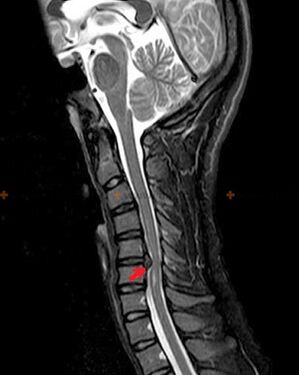

Η οστεοχόνδρωση είναι μια ακτινολογική διάγνωση, αφού λεπτομερής κλινική εικόνα υπάρχει μόνο τη στιγμή της έξαρσης, ενώ όταν ένα άτομο βρίσκεται σε πλήρη υποκειμενική ευεξία μπορεί να εμφανιστούν αλλαγές στη σπονδυλική στήλη. Χωρίς ακτινογραφία, μπορεί κανείς να μιλήσει μόνο για υποψία οστεοχόνδρωσης, καθώς παρόμοια συμπτώματα μπορεί να προκληθούν και από άλλες ασθένειες (μυοσίτιδα, σπονδυλική νεοπλασία κ.λπ.).

Για τη διάγνωση της οστεοχόνδρωσης χρησιμοποιούνται οι ακόλουθες μέθοδοι εξέτασης: ακτινογραφία (κατά προτίμηση με λειτουργικές εξετάσεις), MSCT και MRI. Η τελευταία μελέτη είναι η πιο προτιμότερη καθώς επιτρέπει μια πολύ σαφή απεικόνιση της κατάστασης των μεσοσπονδύλιων δομών.

Τα σημάδια της οστεοχονδρωσίας με ακτίνες Χ περιλαμβάνουν τις ακόλουθες αλλαγές στη σπονδυλική στήλη:

- Μειωμένο ύψος των μεσοσπονδύλιων δίσκων.

- Παρουσία οριακών οστικών αναπτύξεων.

- Παραβίαση της θέσης των σπονδύλων μεταξύ τους.

- Παραμορφώσεις σπονδυλικών σωμάτων και τόξων κ.λπ.

Η παρουσία των αλλαγών που περιγράφονται παραπάνω, καθώς και οι αλλαγές στη δομή του μεσοσπονδύλιου δίσκου που ανιχνεύονται με MSCT και MRI, χρησιμεύουν ως αξιόπιστα σημάδια της παρουσίας οστεοχονδρωσίας.